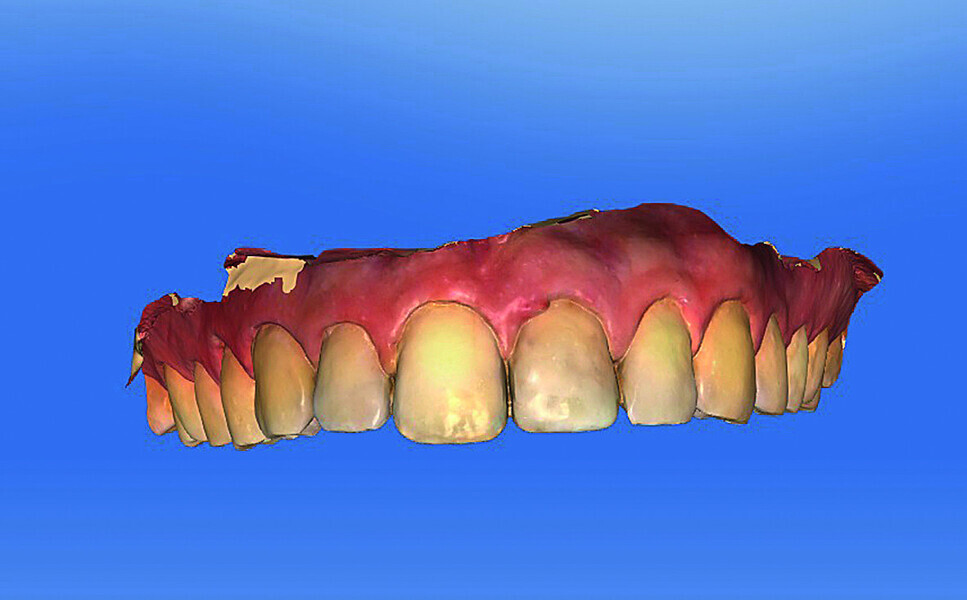

Fig. 3: The initial situation in 3-D in the Sidexis 4

imaging software (Dentsply Sirona) showed good apical bone substance with the possibility of immediate implantation.